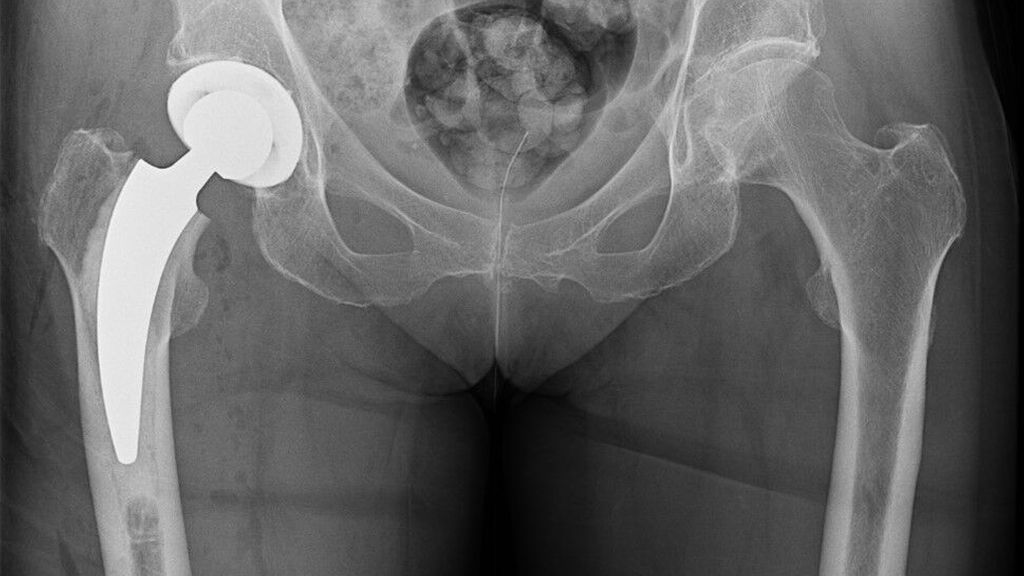

Seit fünf Jahren bietet die in Lüdinghausen, Deutschland, ansässige Firma ARTIQO neben zwei zementfreien Kurzschäften auch die Option eines zementierten Kurzschaftes (A2®) an (Abb.2). Nach EPRD-Daten wurden im Zeitraum von 2020 bis 2023 insgesamt 403 Patienten mit einem Durchschnittsalter von 79 Jahren (74–83 Jahre) damit versorgt.16 Der Anteil der Implantation bei Frauen lag bei 80%. Nach einem Jahr betrug die Ausfallwahrscheinlichkeit 1,6%.

Seit 2021 werden in der Klinik für Unfallchirurgie und Orthopädie des Johannes Wesling Klinikums, Minden, ältere Patienten, die sich eine dislozierte mediale Schenkelhalsfraktur Garden III oder IV zugezogen haben, mit einer zementierten Kurzschaftprothese versorgt. Als Kopf wird entweder eine unipolare Pfanne oder eine zementfreie Pfanne implantiert. 2023 und 2024 wurde bei insgesamt 174 Patienten eine zementierte Kurzschaftprothese über einen Watson-Jones-Zugang in Rückenlage implantiert. Das Durchschnittsalter lag über 80 Jahre. Es wurden mehr Frauen als Männer behandelt (67,2% weiblich, 32,8% männlich). Fast 70% der Patienten fielen in die ASA-Klassifikation Grad 3 (1,1% ASA 1; 21,3% ASA 2; 70,1% ASA 3; 6,9% ASA 4; 0,6% ASA 5). Insgesamt 84,5% der Patienten erhielten eine Hemiendoprothese, während 15,5% mit einer Totalendoprothese versorgt wurden (Abb. 3,4). Nach der postoperativen unfallchirurgischen Behandlung wurden die Patienten entweder in eine geriatrische Klinik innerhalb oder ausserhalb des Krankenhauses verlegt oder es erfolgte eine stationäre Anschlussrehabilitation. Bis zum Zeitpunkt der Entlassung musste bei vier Patienten aufgrund einer prolongierten Wundsekretion eine Wundrevision durchgeführt werden. Im Rahmen der postoperativen Mobilisation kam es bei einem Patienten zu einer Luxation, die nach Reposition konservativ behandelt wurde. Die operierten Patienten werden aktuell zur Nachuntersuchung eingeladen.